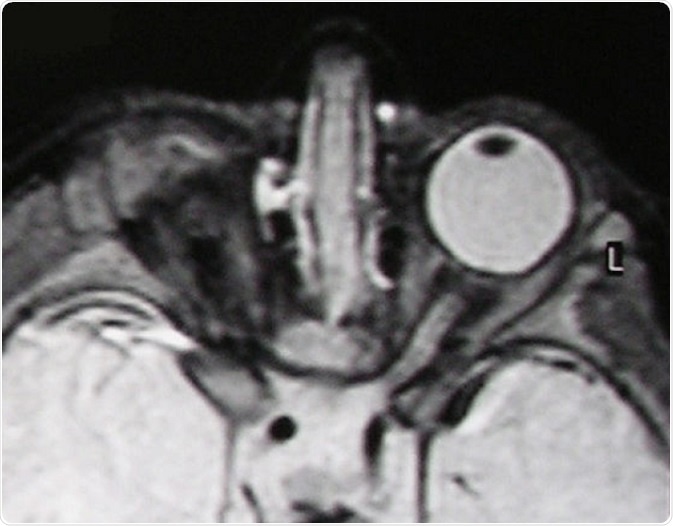

T2-weighted MR scan of a patient with unilateral anophthalmia. Note the presence of amorphous tissue and structures resembling extraocular muscles within the anophthalmic right orbit. The right optic nerve/chiasm junction appears attenuated rather than absent suggesting possible residual optic nerve neural tissue. © Verma AS / Wikimedia Commons.

For example, some genetic mutations lead to anophthalmia (one or no eyes present) or microphthalmia (abnormally small eyes) whereas others lead to cell-specific defects like the absence of rods or cones at the back of the eye, the cells (photoreceptors) that are responsible for detecting light.